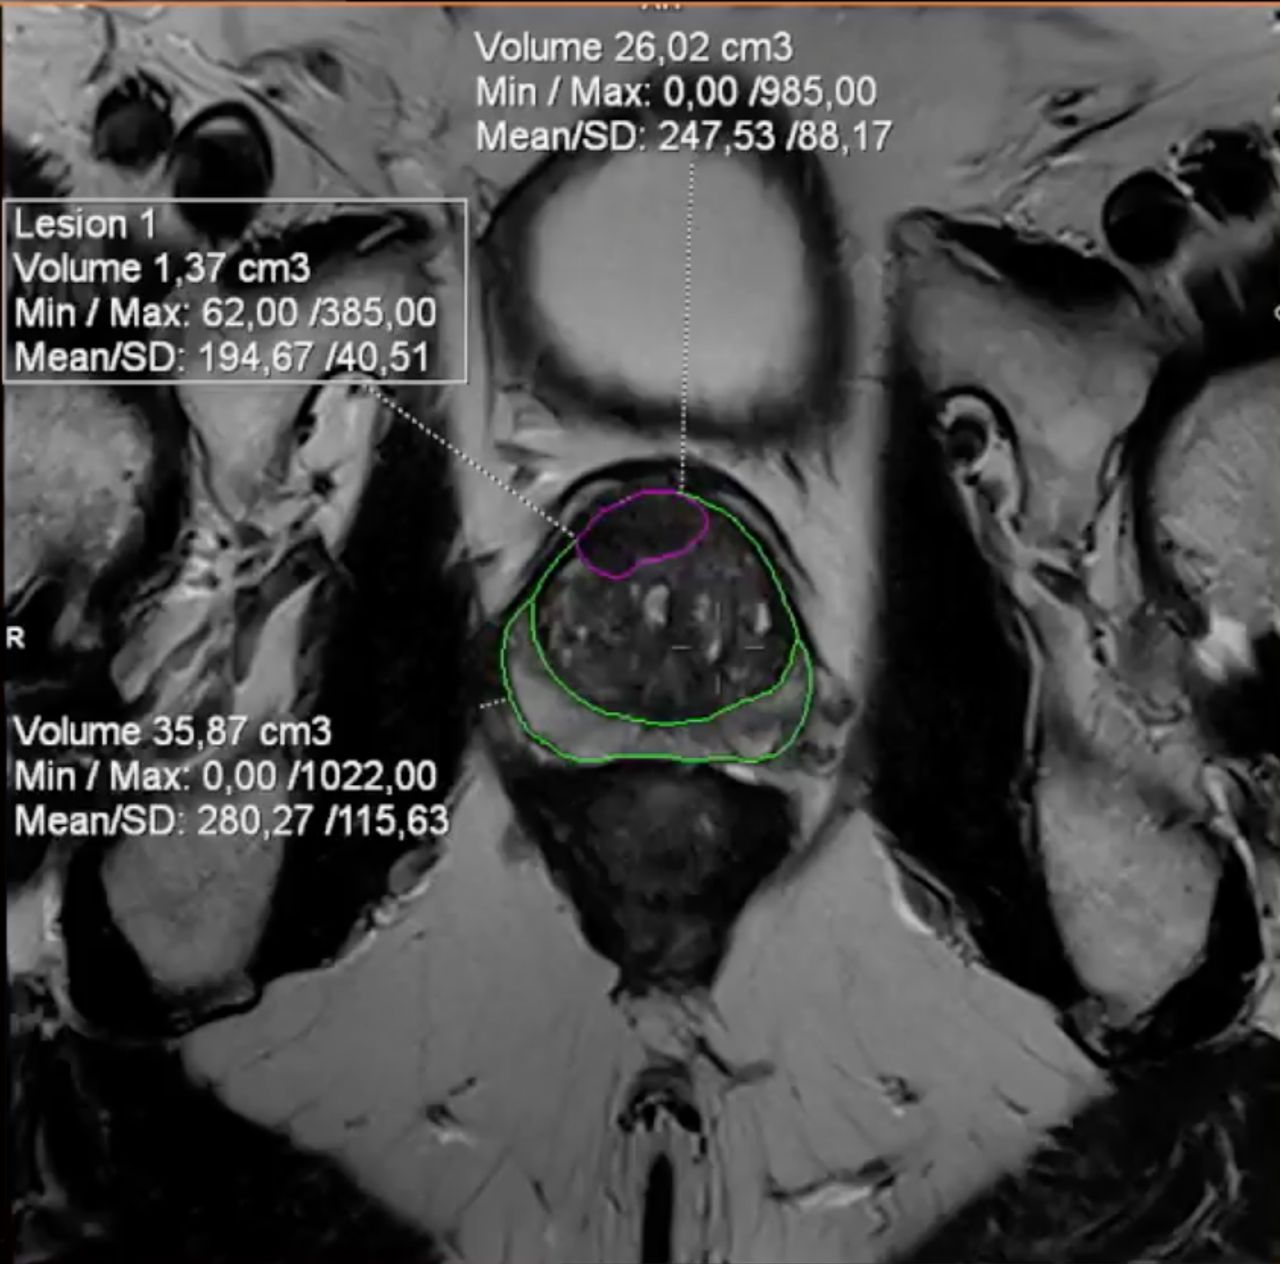

Alfonso-Fausto-8-min-1-650x642

Immagini della prostata vista con la RM (la zona in viola è il tumore)

Alfonso Fausto, facendo riferimento al trial del Prokomb, ha ricordato che i risultati confermano come la Risonanza magnetica possa guidare in modo più preciso le decisioni sulla biopsia, evitando interventi superflui senza perdite in termini di accuratezza.